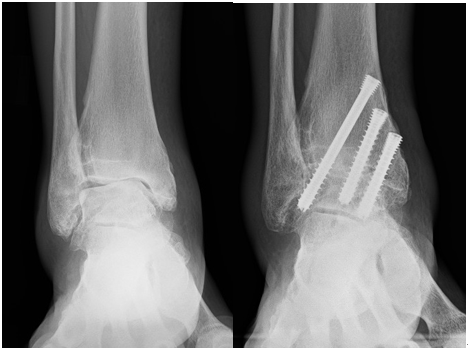

術前 術後

足関節固定術は、最も一般的な変形性足関節症の手術療法です。残存する軟骨を削り、スクリューなどで足関節を固定します。

足は距骨下関節や距舟関節などの多くの隣接関節を有しているため、足関節固定術後も後足部の可動域は残存します。

症例によっては、関節鏡を使用して軟骨を削る低侵襲な手術(関節鏡下足関節固定術)が可能です。

当院では、変形が重度な若年例、ご高齢で人工足関節置換術の合併症リスクが高いと判断される方(糖尿病を合併している方、肥満が強い方、浮腫の強い方など)に主に鏡視下足関節固定術を行っています。

入院期間は、若い方は松葉杖免荷での退院が可能なので1~2週間程度、ご高齢の方は1か月半程度です。術後4~6週程度から短下肢装具を使用し、足を荷重した歩行を開始します。